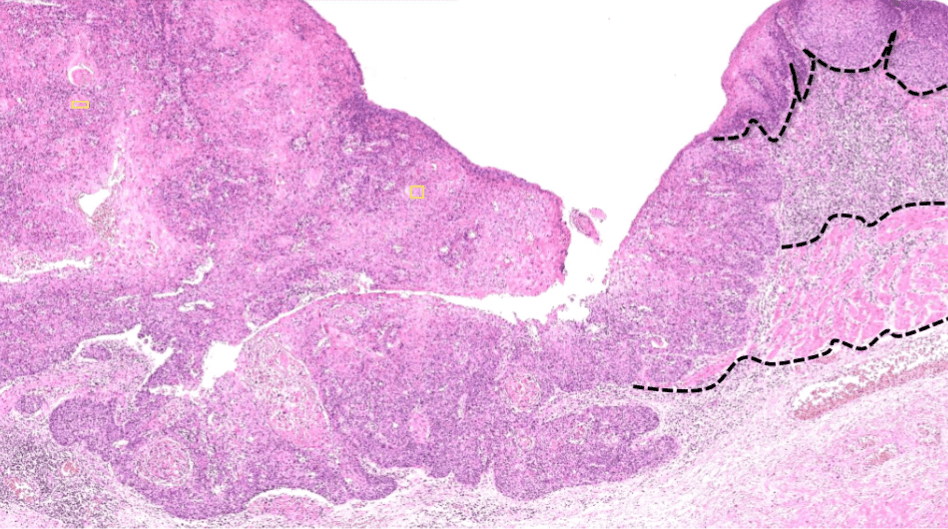

endometrial cancer